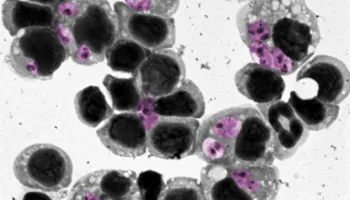

Interplay of human macrophage response and natural resistance of infection by L. (V.) panamensis to pentavalent antimony

PLOS Neglected Tropical Diseases

Author(s): Olga Lucía Fernández, Ulisses Gazos Lopes, Ashton Trey Belew, et. al

UMD Author(s): Najib M. El-Sayed

Innate biosignature of treatment failure in human cutaneous leishmaniasis

Author(s): Maria Adelaida Gómez, Ashton Trey Belew, Deninson Vargas, et. al

Consolidation of a Molecular Signature of Healing in Cutaneous Leishmaniasis Is Achieved during the First 10 Days of Treatment

|

The Journal of Immunology

Author(s): Lina Giraldo-Parra, David E Rebellón-Sánchez, Adriana Navas, et. al